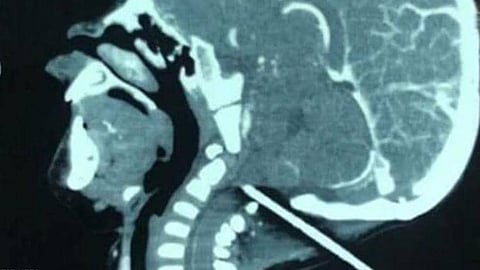

وفوجئ الأطباء برجل يحمل طفلًا وقضيبًا بارزًا من رأسه، وبفحصه بواسطة الأشعة تبيَّن أنَّ القضيب استقرَّ على مسافة ملليمترات معدودة من قاع الجمجمة والأوعية الدموية الحيوية التي تغذيها.